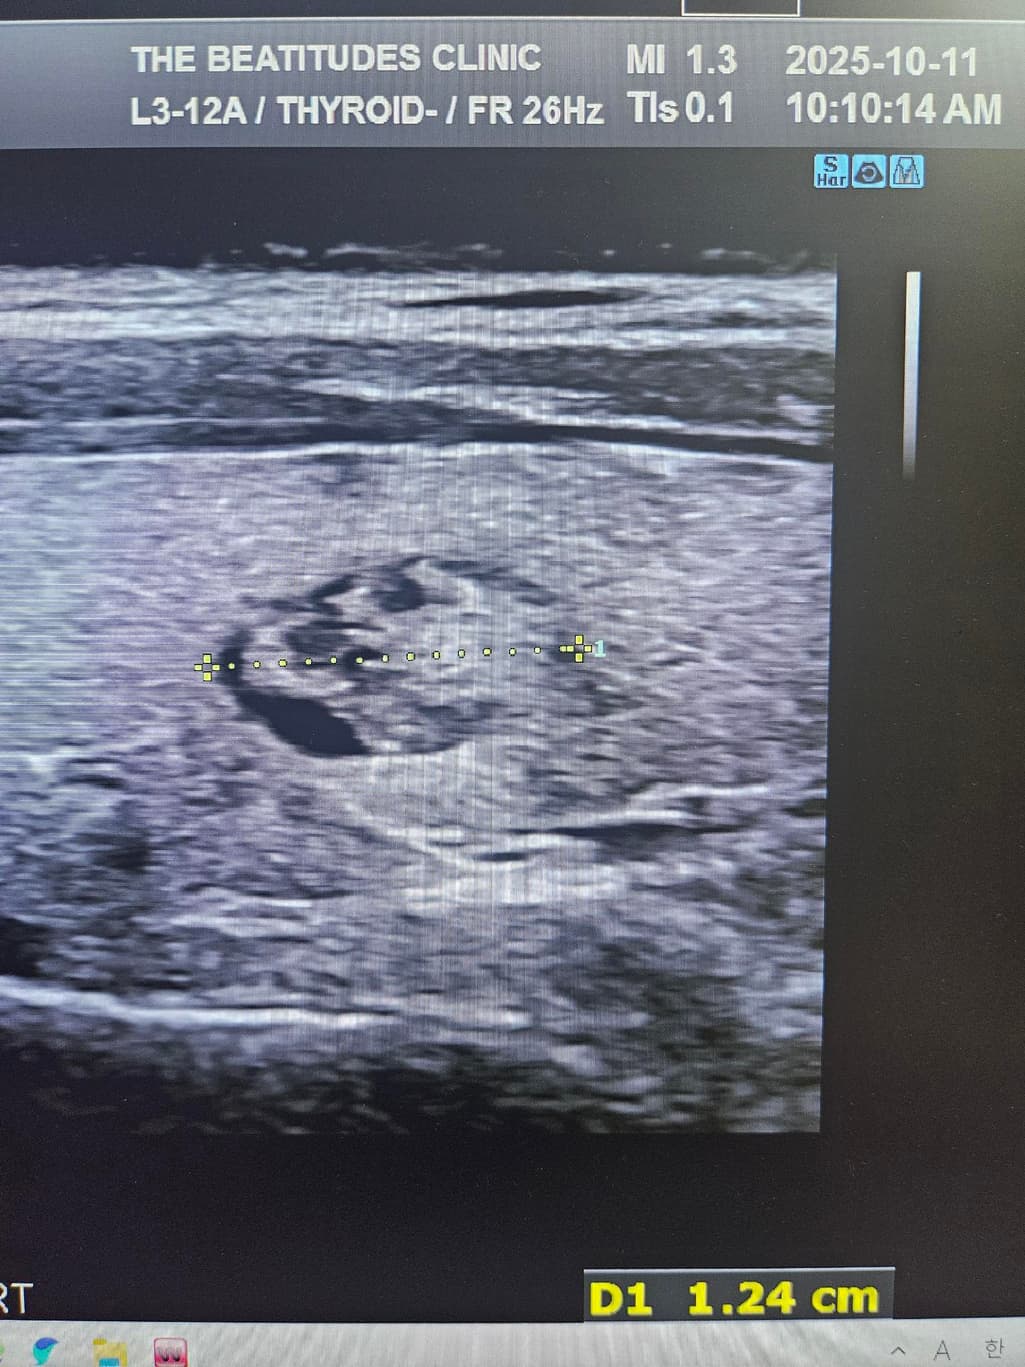

• 2번 째 사진

두번째 사진의 경우는 결절이 보이지 않으며 협부의 두께를 측정한 것 같습니다.